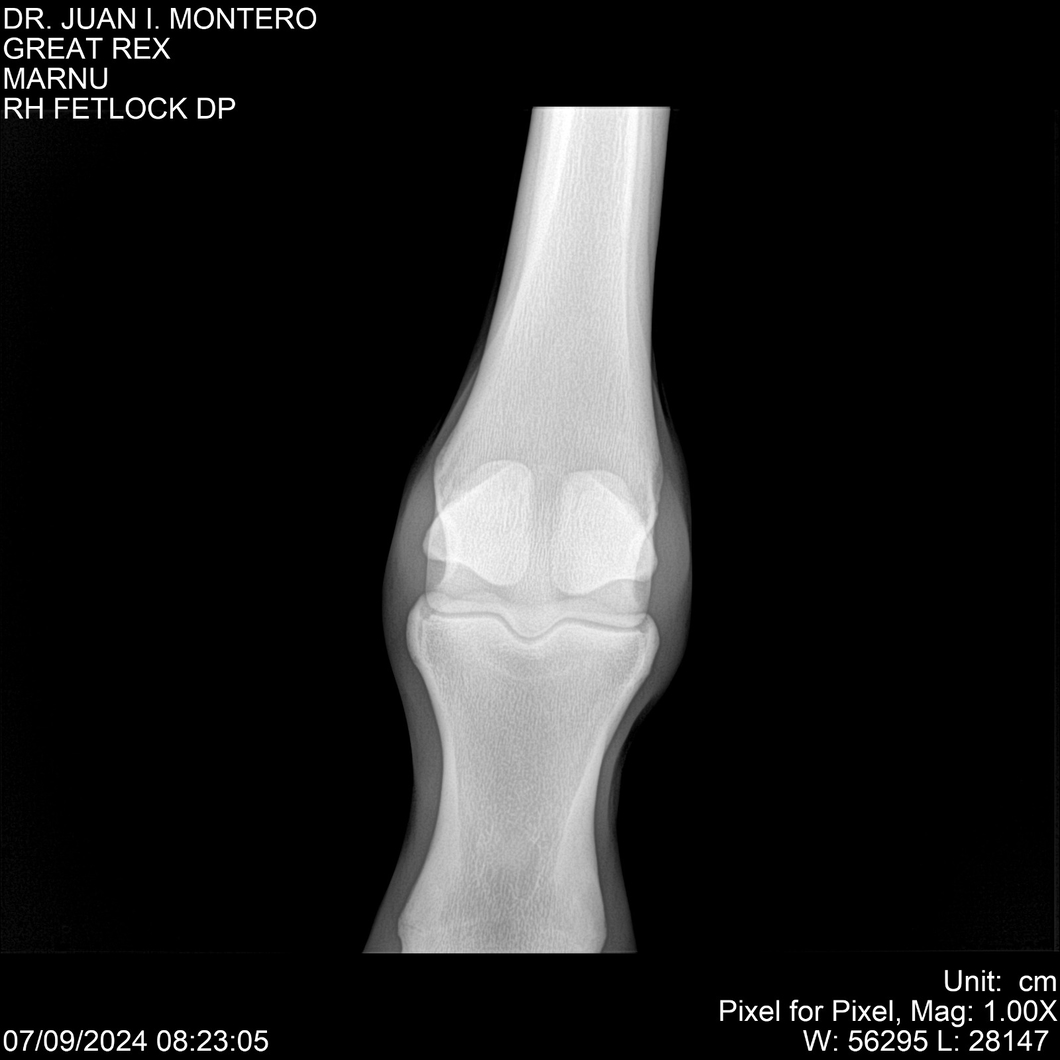

LOTE 4, GREAT REX Lote Anterior Volver al remate Lote Siguiente Ficha Contacto Montevideo - Ficha del Lote Identificador: #282518 Categoría: Yeguarizos Montevideo - 66 Visualizaciones ClicData Contacto Empresa: Abelenda N. R., Walter Hugo Nombre*: Teléfono* : E-mail* : Mensaje Enviar Registrese gratis Este contenido Exclusivo está disponible sólo para usuarios registrados Ingresar